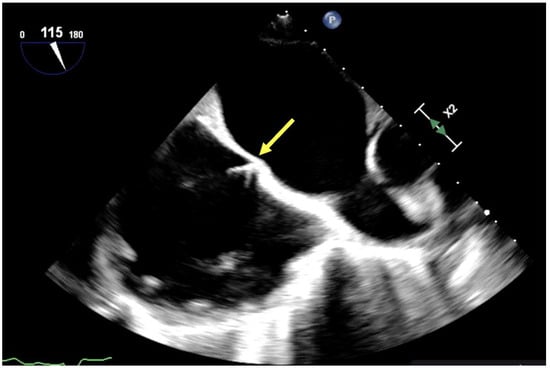

3.2. Dual-Lumen Considerations